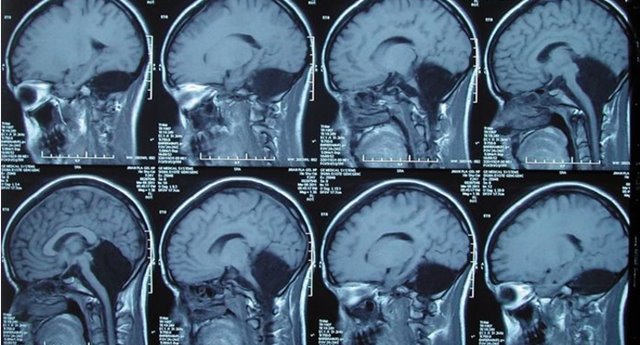

(圖片來源:張榮偉)